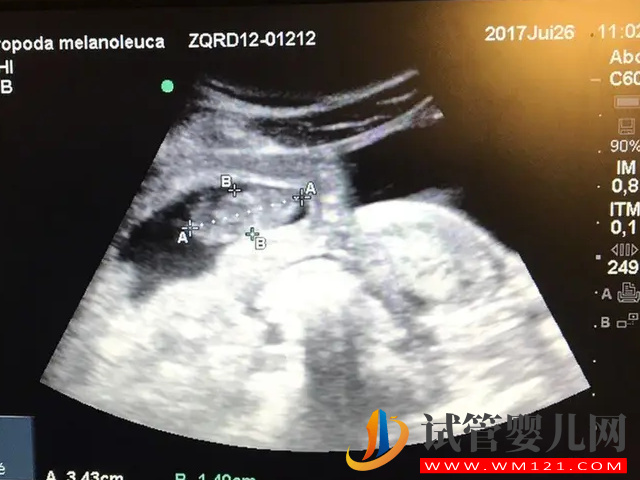

- 1. 有的寶媽說一般在四維彩超的上面頂頭最右邊有兩行字,主要是字母和數(shù)值組成的,第一行是日期,第二行是時(shí)間。如果你發(fā)現(xiàn)第一行是“M”開頭,那就代表是個(gè)男孩,因?yàn)榭赡苁恰癿ale”的縮寫。如果是“F”開頭就是女孩,是“female”的縮寫;

- 2. 還有的寶媽的四維彩超單上很小英文字母“Qualhigh”,如果跟的是數(shù)字“1”那么就是女孩,如果跟的是“2”就是男孩;

- 3. 看四維彩超單上的數(shù)據(jù)也可以看男女,比如說看雙頂徑股骨長,可以用雙頂徑減去股骨長,得出的數(shù)據(jù)大于21mm的話就是兒子,反之就是女兒;